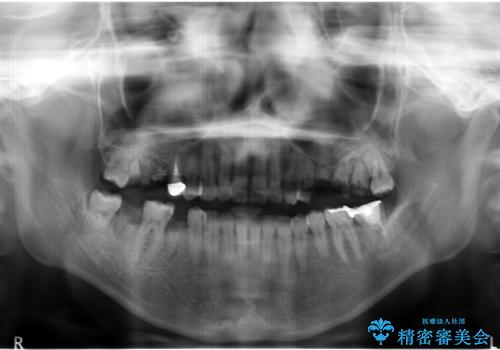

- う蝕により奥歯がボロボロになってしまい、咬むことができないことを主訴に来院された患者様です。

奥歯3本(左上567)はう蝕が深く保存不可能な状態であったため、やむなく抜歯しました。

インプラントも入れ歯も抵抗があるとのご相談により、自家歯牙移植を提案しました。

使っていない親知らず(左上8)を左上7抜歯窩に移植し、支台歯としてブリッジによる補綴治療を行いました。